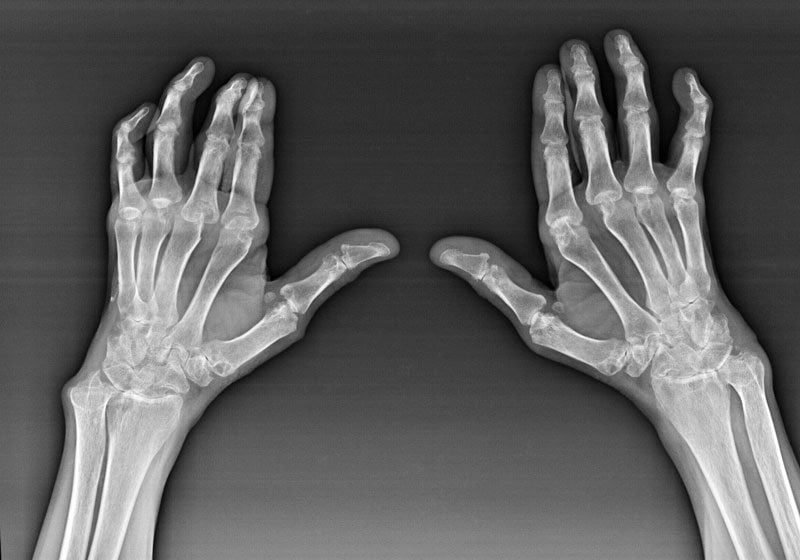

Для диагностики проводится ряд инструментальных и биохимических исследований — МРТ, КТ, рентгенография, артроскопия, определение ревматоидного фактора. Обычно используются консервативные методы терапии: прием препаратов, физиопроцедуры, массаж, ЛФК. При их низкой эффективности или выявлении у больного значительного повреждения суставов назначается хирургическое вмешательство.

- ювенильный, ревматоидный, псориатический артрит. Окончательно неизлечимые заболевания, в основе патогенеза которых лежит сочетание наследственных, аутоиммунных, метаболических факторов. Часто выявляется тугоподвижность неврогенного характера из-за болей, возникающих при попытке сгибания или разгибания суставов;

Скованность мелких и крупных сочленений верхних конечностей становится тревожным сигналом, особенно для стариков и пожилых людей. Она может указывать на развитие полиартроза — медленно прогрессирующего заболевания дистрофического характера, поражающего мелкие суставы фаланг. Для подобного состояния характерно снижение выработки синовиальной жидкости. Потеря амортизационной смазки костных поверхностей приводит к разрушению хрящевых тканей и образованию мелких трещин в костных структурах. В них начинают откладываться соли кальция, стимулируя формирование костных шипов и наростов, сужение суставной щели.

Все суставные заболевания хорошо поддаются лечению только на начальной стадии при появлении первых признаков тугоподвижности. При отсутствии врачебного вмешательства через несколько лет развивается анкилоз — частичная или полная неподвижность сочленений рук. Поэтому появление утренней скованности любого сустава — сигнал для немедленного обращения к врачу.